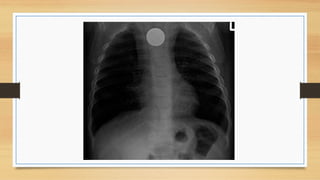

Caso 4

•  Niño de 15 años alto y delgado, fumador, que vuelve de vacaciones (buceo y

viaje en avión) y acude a urgencias por dolor en lado dcho. de tórax que

aumenta con la inspiración y disnea que va en aumento desde el día anterior.

•  Exploración : disminución de ruidos respiratorios en hemitórax derecho.

•  Rx de tórax

Neumotórax

•  Aire en la cavidad pleural que causa colapso pulmonar.

•  Puede ser espontáneo (primario o secundario) o adquirido ( traumático o iatrogénico).

•  Es más frecuente en hombres delgados jóvenes.